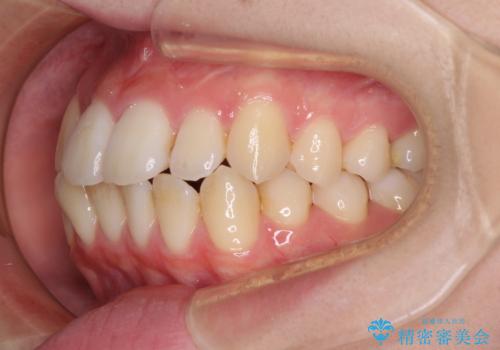

【モニター】前歯の前突感とクロスバイトをインビザラインで改善

- 前歯の突出感とクロスバイトが気になり、インビザラインによる矯正治療を希望して来院された患者様です。

上顎側切歯(上の真ん中から2番目の歯)が舌側転位している場合、インビザラインでは仕上げきれないことが多く、更には無理して動かそうとすると歯髄壊死を起こすリスクが高いと言われています。

インビザラインで歯列を移動する前に、上顎前歯をワイヤー矯正で整え、その後上下歯列をインビザラインにて矯正治療を行うこととしました。

舌側転位している側切歯特有の、切縁の位置が不揃いであったり、根元が内側に引っ込んだ状態であったりという、インビザライン独特の仕上がりになることなく、きれいに整った歯列とすることができました。